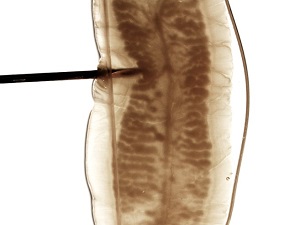

Case #489 – April, 2019

A teenage female college student from Texas observed a foreign object in her feces and took it to her school health clinic. She had no complaints of illness and did not present with any clinical symptoms. She also did not report any domestic or foreign travel history. The specimen was sent to the state public health laboratory for examination. Stool samples were ordered and tested by the school health clinic but the results were all negative for ova and parasites (O&P). The state lab then sent images of the foreign object as well as the physical specimen to the CDC for identification. Figures A and B show what the student observed in her stool. What test method would be useful in identifying the object? What is your diagnosis? Based on what criteria?

Figure B